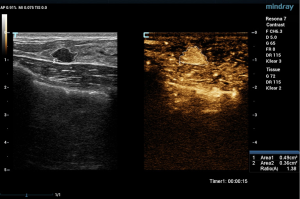

Mindray Resona7, LOGIQ E9, and MyLab Class C Color Doppler sonography were used (with probe models of L11-3U; ML6-15, 9L; and LA523 and LA522, and with contrast agent of SonoVue (Bracco Corporate, Shanghai, China). Before angiography, all patients agreed and signed informed consent. The patient was placed in the supine position with both hands raised to expose the breast fully. First, grayscale ultrasonography scanned the mammary gland, and if any nodule was found, the characteristics of the nodule, including the position, maximum diameter, shape, edge, internal echo, and rear echo were recorded. Then the section of the nodule, with the most abundant blood supply, was selected for angiographic examination. After 3.0 mL, SonoVue was injected through the cubital vein mass, 5 mL normal saline was rapidly injected for flushing, and a timer and dynamic storage function were started while the contrast agent was injected. During the examination, we asked the patient to breathe calmly, kept the selected section unchanged, and did not press the probe.

Two experienced senior physicians tested all ultrasound images without knowledge of the patient’s clinical data. When the two did not agree, a consensus was reached through discussion. The dynamic contrast images stored in the hard disk of the instrument were played back, and the images were frozen when the contrast intensity of the nodule reached its peak. The grayscale image and the contrast image of the nodule were tracked, respectively (Figure 2). The area ratio before and after contrast was calculated, and the average value was taken after repeated measurements for three times. When the nodule displayed iso-enhancement with the surrounding tissue, and the boundary was unclear, the default area ratio before and after nodule contrast was 1.